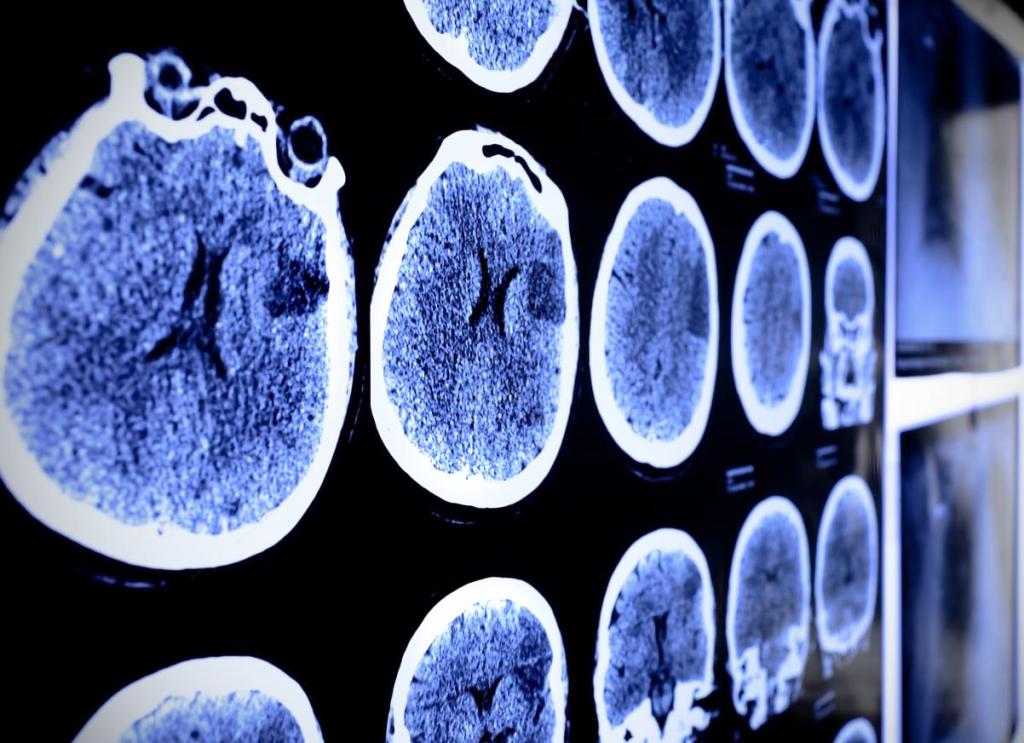

El estudio, publicado en la revista Nature Medicine, incluyó a 351 pacientes que habían sido hospitalizados por complicaciones graves de la COVID-19 y un grupo de control de 2,927 personas. Los investigadores analizaron los datos de tomografías cerebrales, análisis de sangre y evaluaciones cognitivas para determinar si había evidencia objetiva de deterioro mental a largo plazo en los pacientes.

Además, las tomografías cerebrales mostraron una reducción en el volumen cerebral en áreas clave del cerebro, sugiriendo que la enfermedad no solo afecta a los pulmones, sino que también tiene un impacto directo en el sistema nervioso central. Paralelamente, los análisis de sangre revelaron niveles elevados de proteínas asociadas con lesiones cerebrales en estos pacientes. Esto refuerza la hipótesis de que la COVID-19 grave puede generar daños cerebrales que persisten mucho tiempo después de que la infección inicial haya sido controlada.